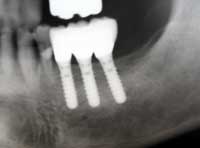

| 術前 | ソケットリフト手術 | 術後2年歯根周囲骨造成良好 |